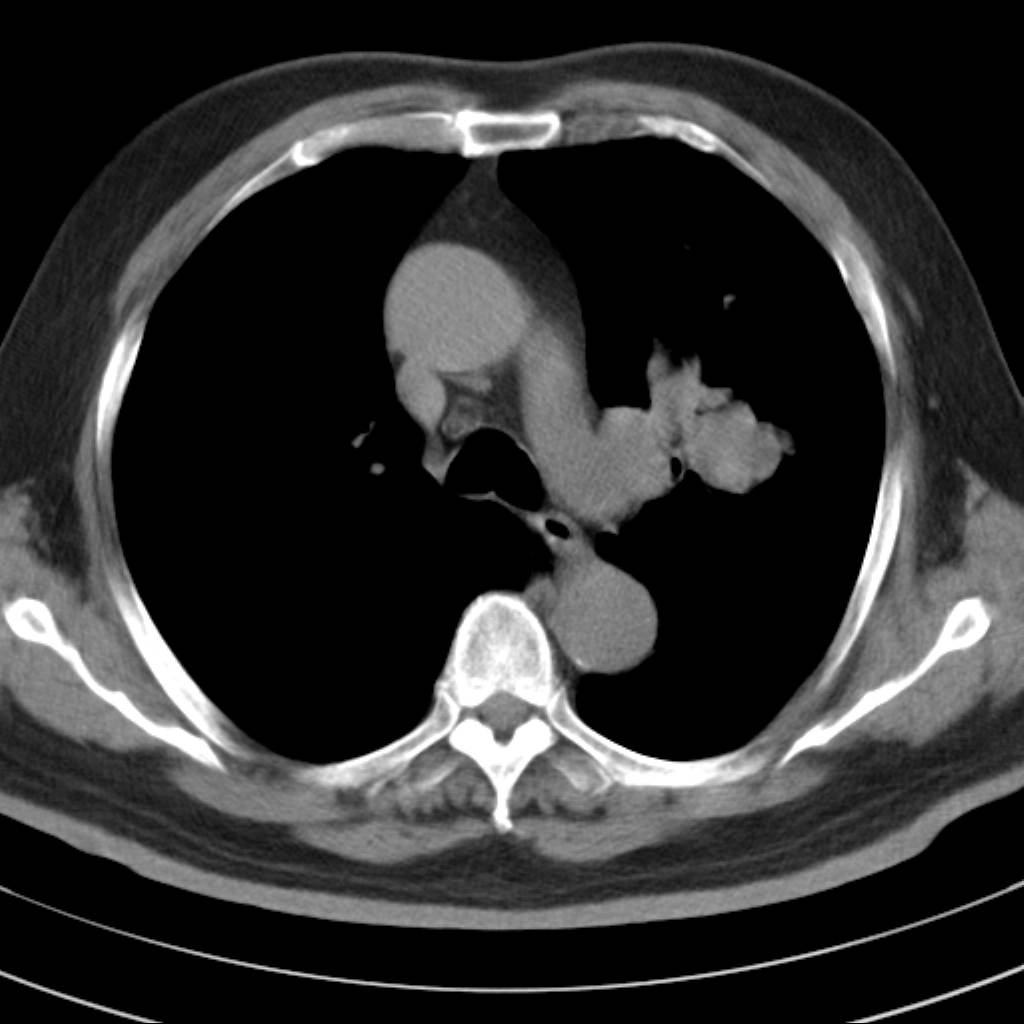

左肺动静脉畸形,肺动静脉畸形(pavms)是肺血管发育异常,是肺动脉与肺静脉直接相通形成短路,通常包括一条供血动脉及一条或数条引流静脉,以及他们之间的异常血管团。约70%的患者伴发遗传性出血性毛细血管扩张症。 影像检查的目的在于确定病灶位置、大小、形态、数目。x线可表现为:1.结节型(直径小于3cm)2.团块型(直径大于3cm)3.弥漫型(肺内散在逗点状影),以团块状居多。 ct扫描可见单发或多发肺内结节,有的有蜿蜒迂曲的团块影,边缘光滑、锐利,增强ct扫描可见增粗、扭曲的血管影和/或类圆形的增粗的血管断面,甚至供血动脉及引流静脉。

平扫似avm,建议增强扫描。

支持考支气管扩张伴粘液栓,但导致粘粘液栓的病因有待进一步检查。支持左上叶支气管基部肿物,肺癌可能性大,但肿块似与肺动脉右支保持良好的伙伴关系,不除外为肺动脉扩张所致,建议增强。